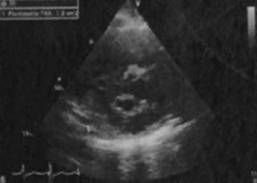

Puérpera de 32 años con antecedente de dos embarazos previos complicados. El primero, con preeclampsia severa con muerte del feto in utero por causa desconocida a las 38 semanas de gestación; el segundo embarazo cursó normoevolutivo durante la gestación hasta el expulsivo donde se realizó un parto instrumentado con fórceps. Inició siete días previos a su ingreso con edema de miembros pélvicos no doloroso, ascendente, caliente, blando; a las 24 horas se agregó cefalea parietal bilateral, pulsátil, con intensidad 8/10, acompañada de náusea con vómito de contenido gastrobiliar y disnea de pequeños esfuerzos. Acudió a facultativo, quien detectó cifras tensionales de 130/80 y la refirió a un hospital de tercer nivel. Se internó en el Servicio de Materno-Fetal con sospecha diagnóstica de trombosis venosa profunda. Cursó con deterioro súbito de la función pulmonar manifestado con hipoxemia severa; requirió de ventilación mecánica invasiva por desarrollo de edema agudo pulmonar; por taller hemodinámico se documentó falla cardiaca con datos de disfunción diastólica, que precisó de inotrópico y vasopresores. Se recibió en la terapia intensiva sedada con RAMSAY 5, eutérmica (temperatura: 37.5 oC), taquicárdica (122 latidos/minuto), hipotensa (89/47 mmHg), aún con apoyo de vasopresina y norepinefrina, manteniendo presiones medias > 70 mmHg. Con precordio hiperdinámico con levantamiento para esternal bajo, se palpó chasquido de cierre pulmonar. Ruidos cardiacos disminuidos con reforzamiento del segundo ruido y soplo holosistólico II/VI en el foco mitral, sin galope o frote pericárdico; trazo electrocardiográfico: con fibrilación auricular de respuesta ventricular alta (Figura 1), taller hemodinámico con patrón hiperdinámico. Con soporte ventilatorio mecánico invasivo, campos pulmonares hipoventilados con estertores en velcro, abdomen globoso con aumento del timpanismo, peristaltismo disminuido, con oliguria en 0.3 cm3/kg/hora. Se realizó una radiografía de tórax con infiltrado en alas de mariposa, además de cono pulmonar prominente, elevación del hemidiafragma derecho (Figura 2). Laboratorios: antiestreptolisinas 53 UI/m, factor reumatoide 20.5, procalcitonina 4.120 ng/mL, CPK 281 µ/L, CKmb 29 U/l, dímero D 9898 ng/mL, péptido natriurético cerebral: 863.90 pg/mL, velocidad de eritrosedimentación y proteína C reactiva aumentadas. Se realizó interconsulta con el Servicio de Cardiología, quien llevó a cabo ecocardiograma transtorácico, con estenosis valvular mitral con área de 1.2 cm (Figura 3) y gradiente transvalvular de 36 mmHg, con probable etiología reumática. Hipertensión arterial pulmonar severa con presión sistólica del ventrículo derecho (PSVD) de 83 mmHg y función sistólica biventricular conservada; dilatación del ventrículo derecho con excursión sistólica del anillo tricuspídeo (TAPSE) de 23 mm; no se pudo evaluar de forma adecuada el estado de la válvula aórtica, solo se encontró gradiente ligeramente incrementado, que se puede atribuir a hiperdinamia. Sin signos clínicos de tromboembolia pulmonar, fracción de expulsión del ventrículo izquierdo (Fevi) de 80% (Figura 4). El Servicio de Nefrología integró el diagnóstico de lesión renal aguda prerrenal AKIN III y el Servicio de Neumología corroboró ausencia de datos de trombosis pulmonar, aun con la elevación del dímero D (9898). Se instauró manejo farmacológico con vasodilatadores dinitrato de glicerilo, inotrópico (levosimendam), morfina, diuréticos, betabloqueador, sildenafil (para manejo de hipertensión pulmonar) y terapia de sustitución renal precoz (hemodiálisis) de urgencia para manejo de sobrecarga hídrica. La paciente evolucionó favorablemente a la terapéutica a base de metas de paciente crítico. Se inició el retiro de aminas vasopresores, sildafenil e inotrópico a las 72 horas, sin repercusión hemodinámica, con posterior retiro de la ventilación mecánica al cuarto día de resolver el edema pulmonar. Con mejoría hemodinámica, se realizó una nueva valoración por parte del Servicio de Cardiología, quien la catalogó como estenosis mitral moderada y decidió control ambulatorio. La paciente fue egresada de terapia al octavo día de internamiento, sin repercusión hemodinámica o fallas orgánicas. A la semana inició consulta de forma ambulatoria en el Servicio de Cardiología para programar su tratamiento quirúrgico: valvuloplastia percutánea mitral por balón.